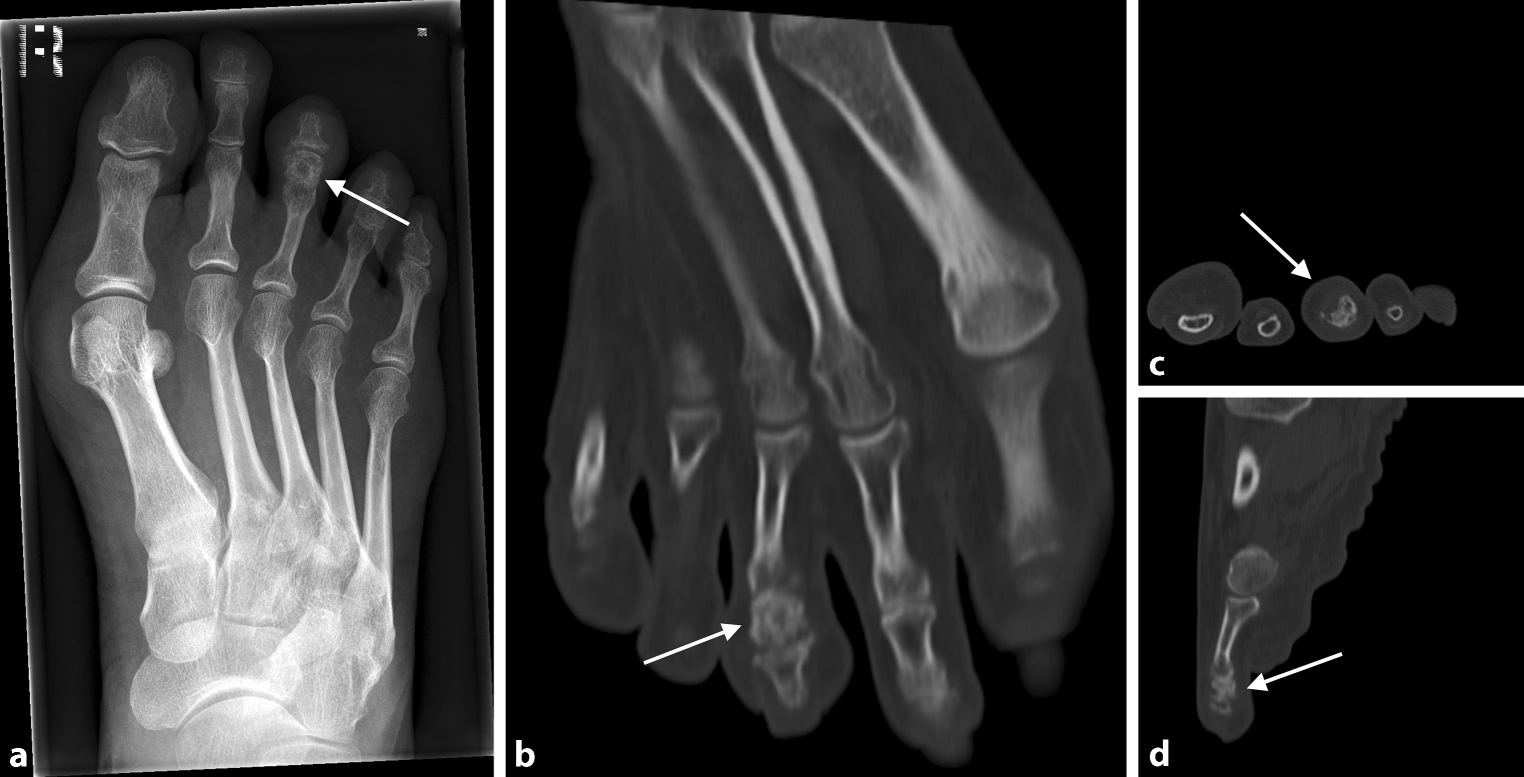

Fig. 3

a 57-year-old female patient with osteoid osteoma of the right foot 3rd middle phalanx. X‑ray with cortical thickening and central osteolytic area occupying the entire middle phalanx of the 3rd ray (arrows pointing at the regions of interest). bd Transverse (b), frontal (c), and sagittal (d) CT scans with expansive process of the distended middle phalanx, partly sclerotic, partly lytic with sporadic cortical destruction and surrounding soft tissue swelling (arrows pointing at the regions of interest)